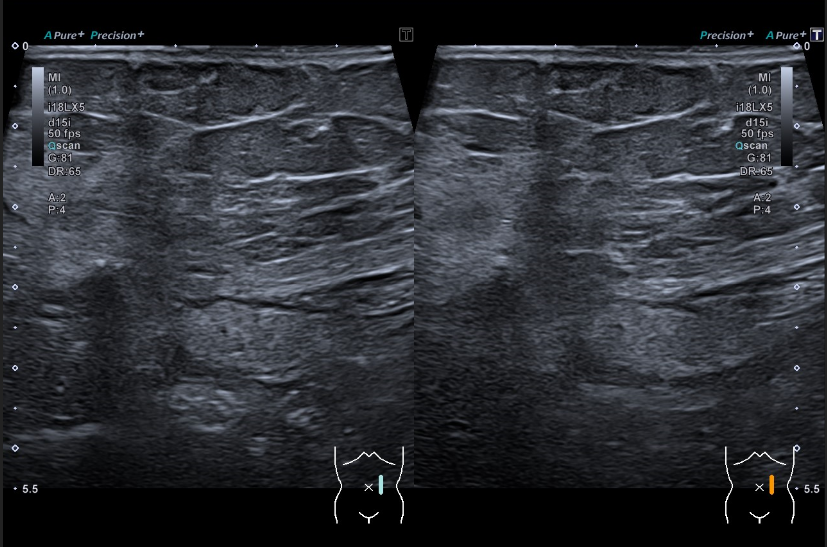

Se realiza una ecografía abdominal en el centro de salud visualizándose una masa hiperecogénica de 15 centímetros, aproximadamente, que parece dependiente del riñón derecho.